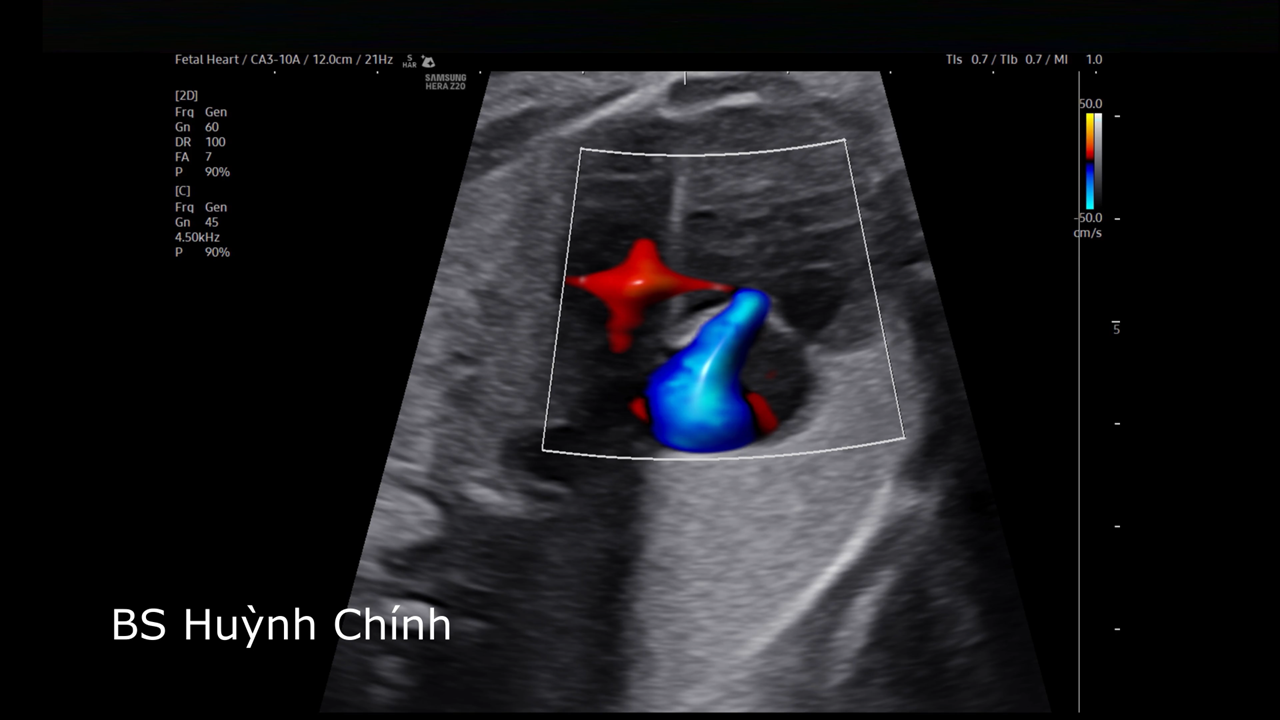

Báo cáo loạt ca co thắt, đóng ống động mạch trước sinh: bệnh lý nguy hiểm nhưng dễ bỏ sót

ThS. BS. Huỳnh Chính

Bệnh viện Từ Dũ